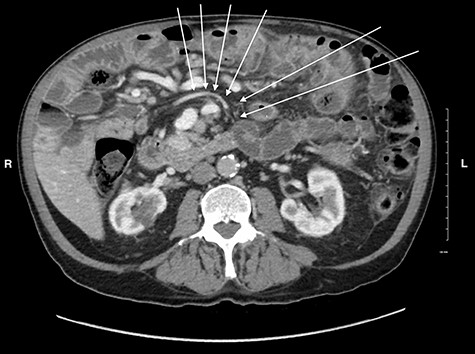

Midgut volvulus is an uncommon disease most often presenting in children, with rare occurrences in adults [3]. It is characterized by an abnormal rotation of the intestine around a fixed-point. Associated congenital conditions include gastrointestinal malrotation, jejunoileal diverticulosis and a history of abdominal wall defects [5, 6]. Acutely, volvulus can be intermittent or complete, with variable symptoms, leading to obstruction, bowel necrosis and possibly death. Chronic presentations of midgut volvulus can also occur, resulting in recurrent pain, intermittent obstruction and malabsorption over months to years. Due to its rarity in adults and variable presentation, preoperative diagnosis of intestinal volvulus is challenging. Adding to this difficulty, a classic ‘whirlpool sign’ or abnormal superior mesenteric vessel configuration is only present on CT in 30.9 and 58% of cases, respectively [3]. Retrospectively, the right-sided position of the duodenojejunal flexure and slight swirling of small bowel mesentery is visible but clouded by numerous jejunoileal diverticula (Figs 5 and 6).

CT image of the right sided position of duodenojejunal flexure, entering the intraperitoneal cavity on the right side of the abdomen.